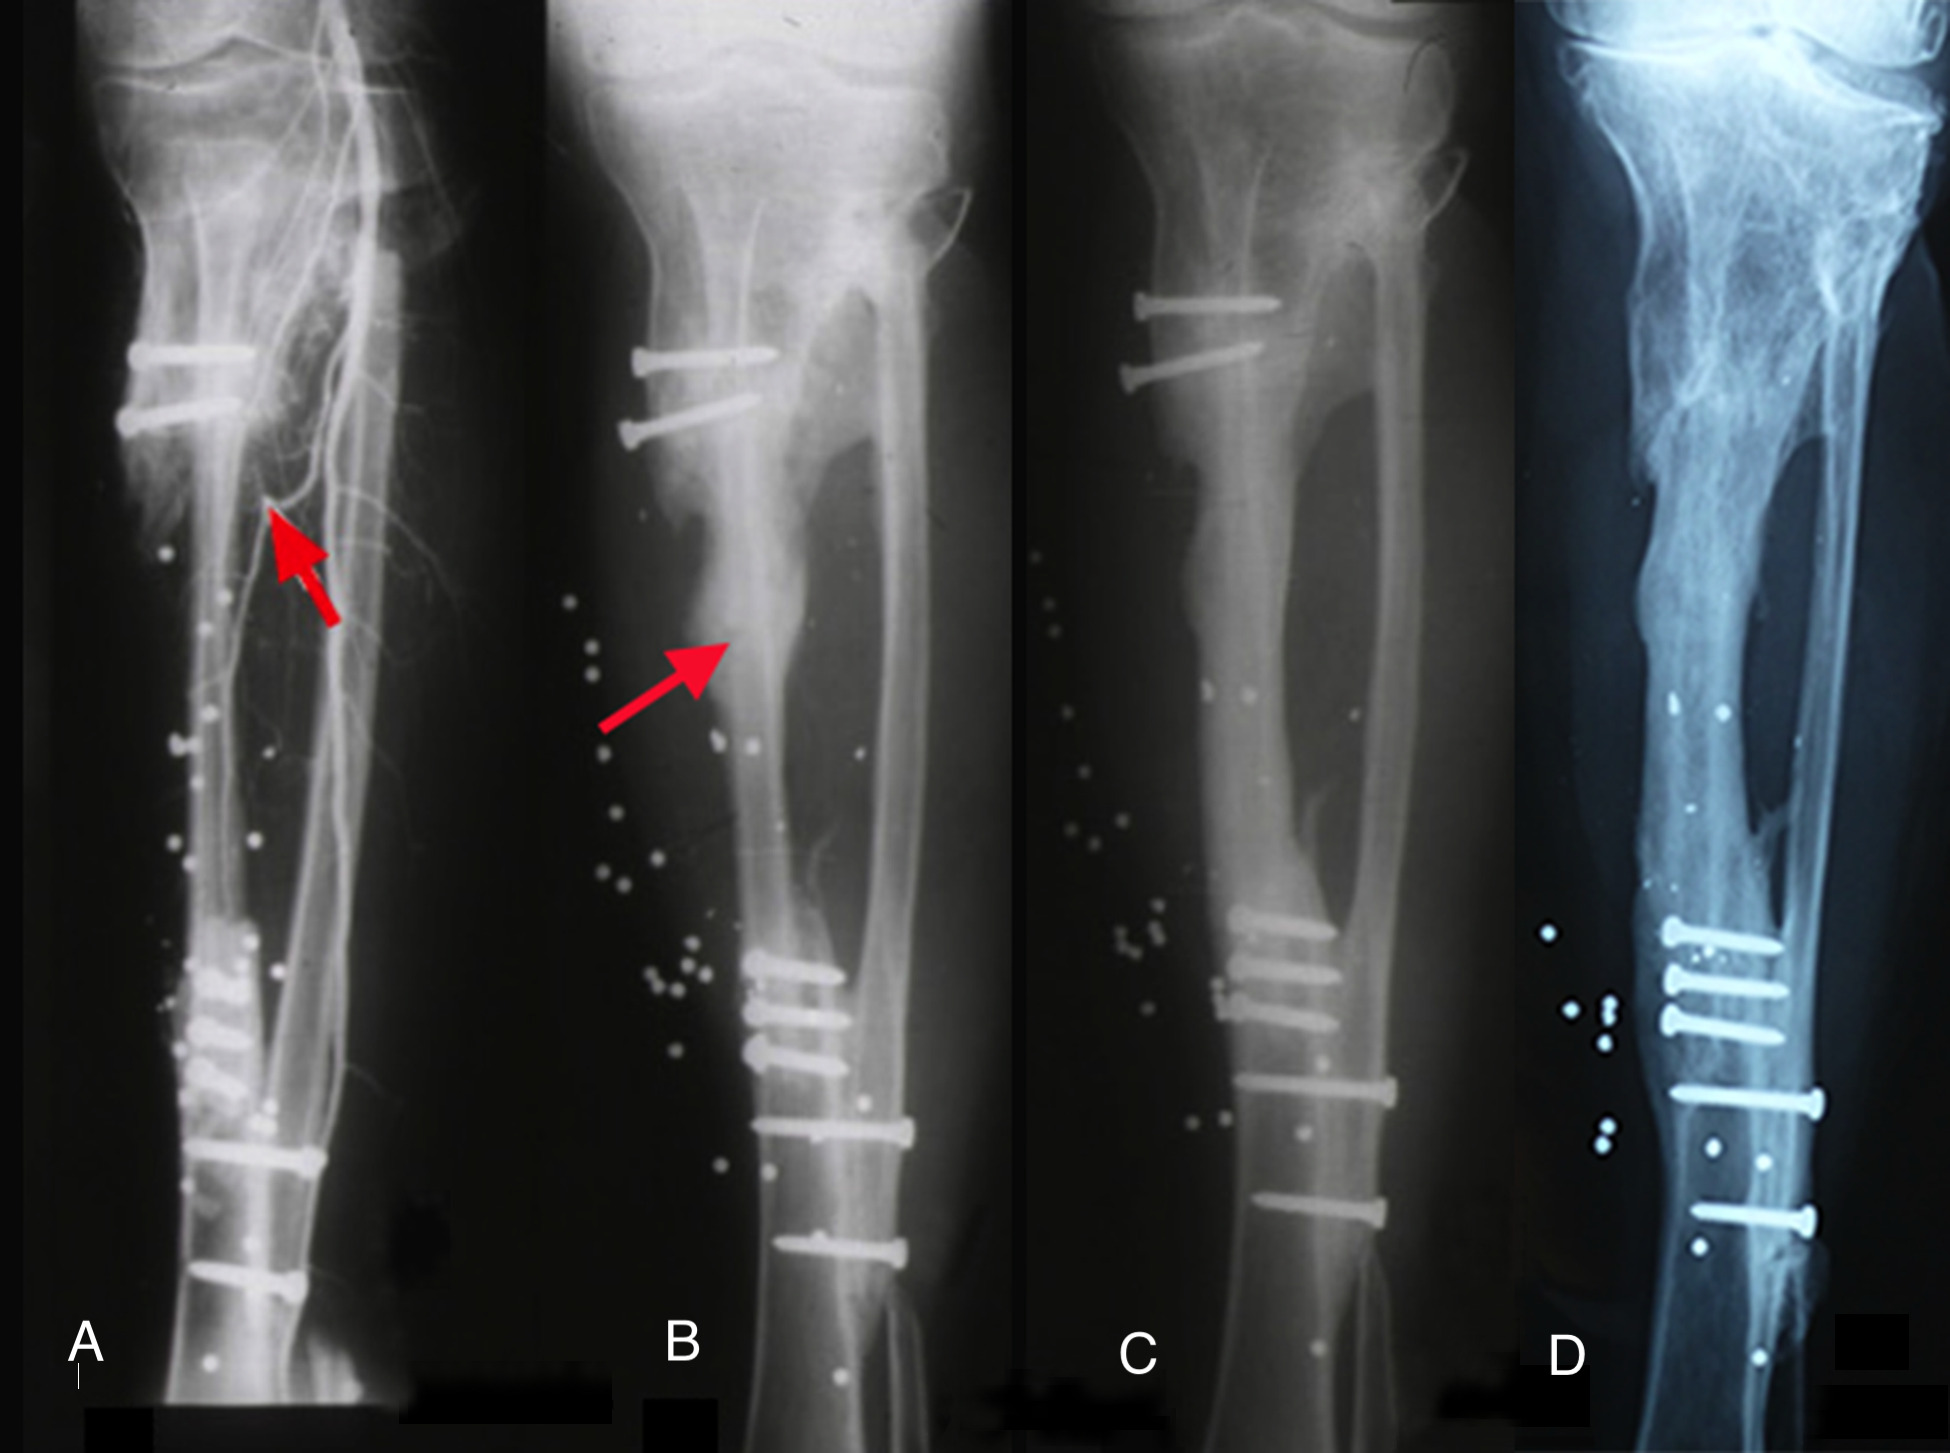

The importance of centralising the fibula within the medullary cavity of the femur or tibia is again reinforced by another case done at the Royal Melbourne Hospital. The fibula was used to reconstruct the femur but fixed rigidly with a plate and screws in Case 14 (Figure 34A). Twelve months later there was union but no sign of hypertrophy of the transplant. Then the plate broke. A Kuntscher nail was inserted from above and down through the medullary cavity of the fibula. It shattered forming a row of ‘bangles’ around the nail (Figure 34B). Two years later, having walked on his ‘box of bones skewered by the K-nail,’ he was located and the leg radiographed. Except for one level, there was union and hypertrophy of all bone bangles (Figure 34C).